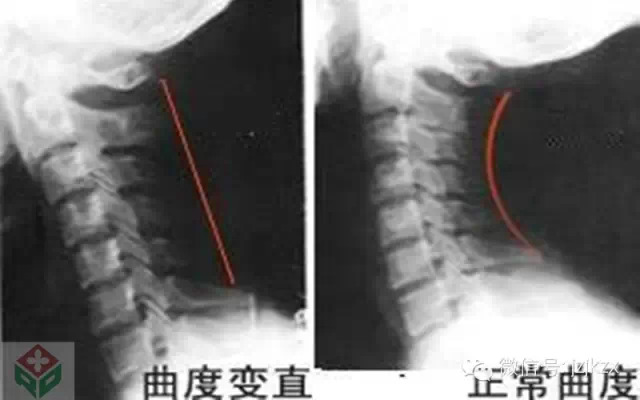

常言道:“防微杜渐”,千万不要等到颈椎病恶化到需要手术治疗的程度。人们在睡眠时颈部肌肉基本完全放松,是重塑颈椎的最好时机。因此,正确选择枕头来重塑颈椎尤为重要。枕头过高,过低,过软都会引起颈椎病或和加重本病。过高的枕头将强迫颈椎过度弯曲,损害下颈段肌肉和关节。过低的枕头则会破坏颈椎弯曲,不利于上颈椎的休息。过软的枕头会使颈椎变性,受伤害。医生给病人的首项建议是“换健康枕头”!